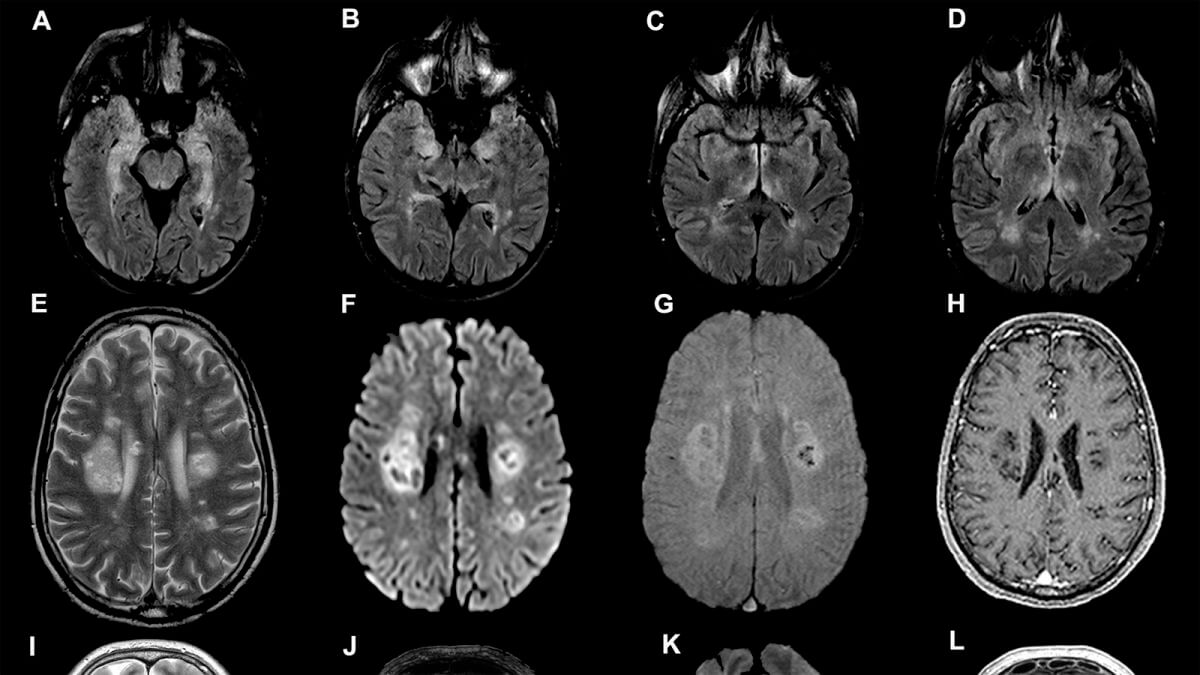

Коронавирус приводит к серьезным повреждениям в мозге.